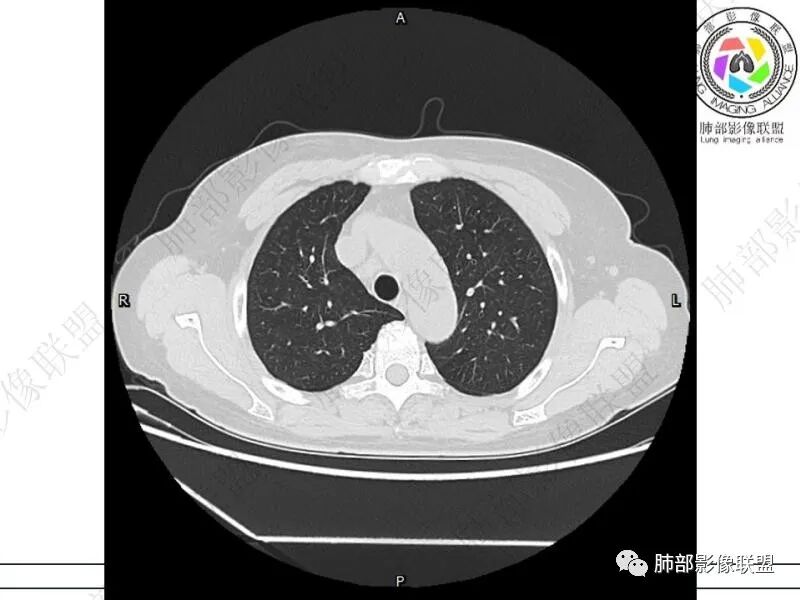

摘星空竹子:两肺胸膜下多发实性结节、磨玻璃影及实变影,短期复查病变有所进展,考虑感染性病变,隐球菌可能,患者有右半结肠癌手术史,转移不能除外。

简单:双肺及胸膜下多发小结节,双下肺胸膜下宽基底团块影,短期内病灶进展考虑炎性病变,隐球?患者ca术后,双肺小结节随诊除外转移

丽:双肺下叶胸膜下多发片状高密度影,边缘模糊不清,内可见支气管穿行,病变长轴平行于胸膜,考虑感染性病变,隐球菌

媛:肠癌术后,免疫力低下。两肺胸膜下结节及实变影,实变影长轴平行于胸膜,密度均匀,边界偏清,周围有晕征,短期复查进展,虽隐球菌荚膜抗原检测阴性,还是考虑隐球菌,鉴别OP

谢加平:结肠癌术后史,两肺胸膜下多发结节及斑块实变病灶,实边边界平直征(亚急性和慢性病变过程),双肺下叶后基底段胸膜下为甚,与胸膜平行特点,见支气管充气征,边缘模糊的GG0,首诊2022年11月18日肺部CT,与治疗11月28日对比,病灶未吸收,双肺下叶胸膜下病灶有侧向融合特点,综合分析符合炎性肉芽肿,隐球菌感染。

老年女性,结肠癌术后。两下肺胸膜下为主片状实变,右下肺短期复查融合且病灶长轴平行于胸膜,实变内可见支气管充气征,边缘磨玻璃晕,另两肺内胸膜下散在数枚小结节状、楔形实性灶。考虑感染性病变,隐球菌可能,鉴别肺转移。

2.影像特征:双肺胸膜下多发实性结节、磨玻璃影及实变影,胸膜下优势分布、晕征、胸膜下脂肪间隙存在,部分病灶边界平直征,有侧向融合趋势。